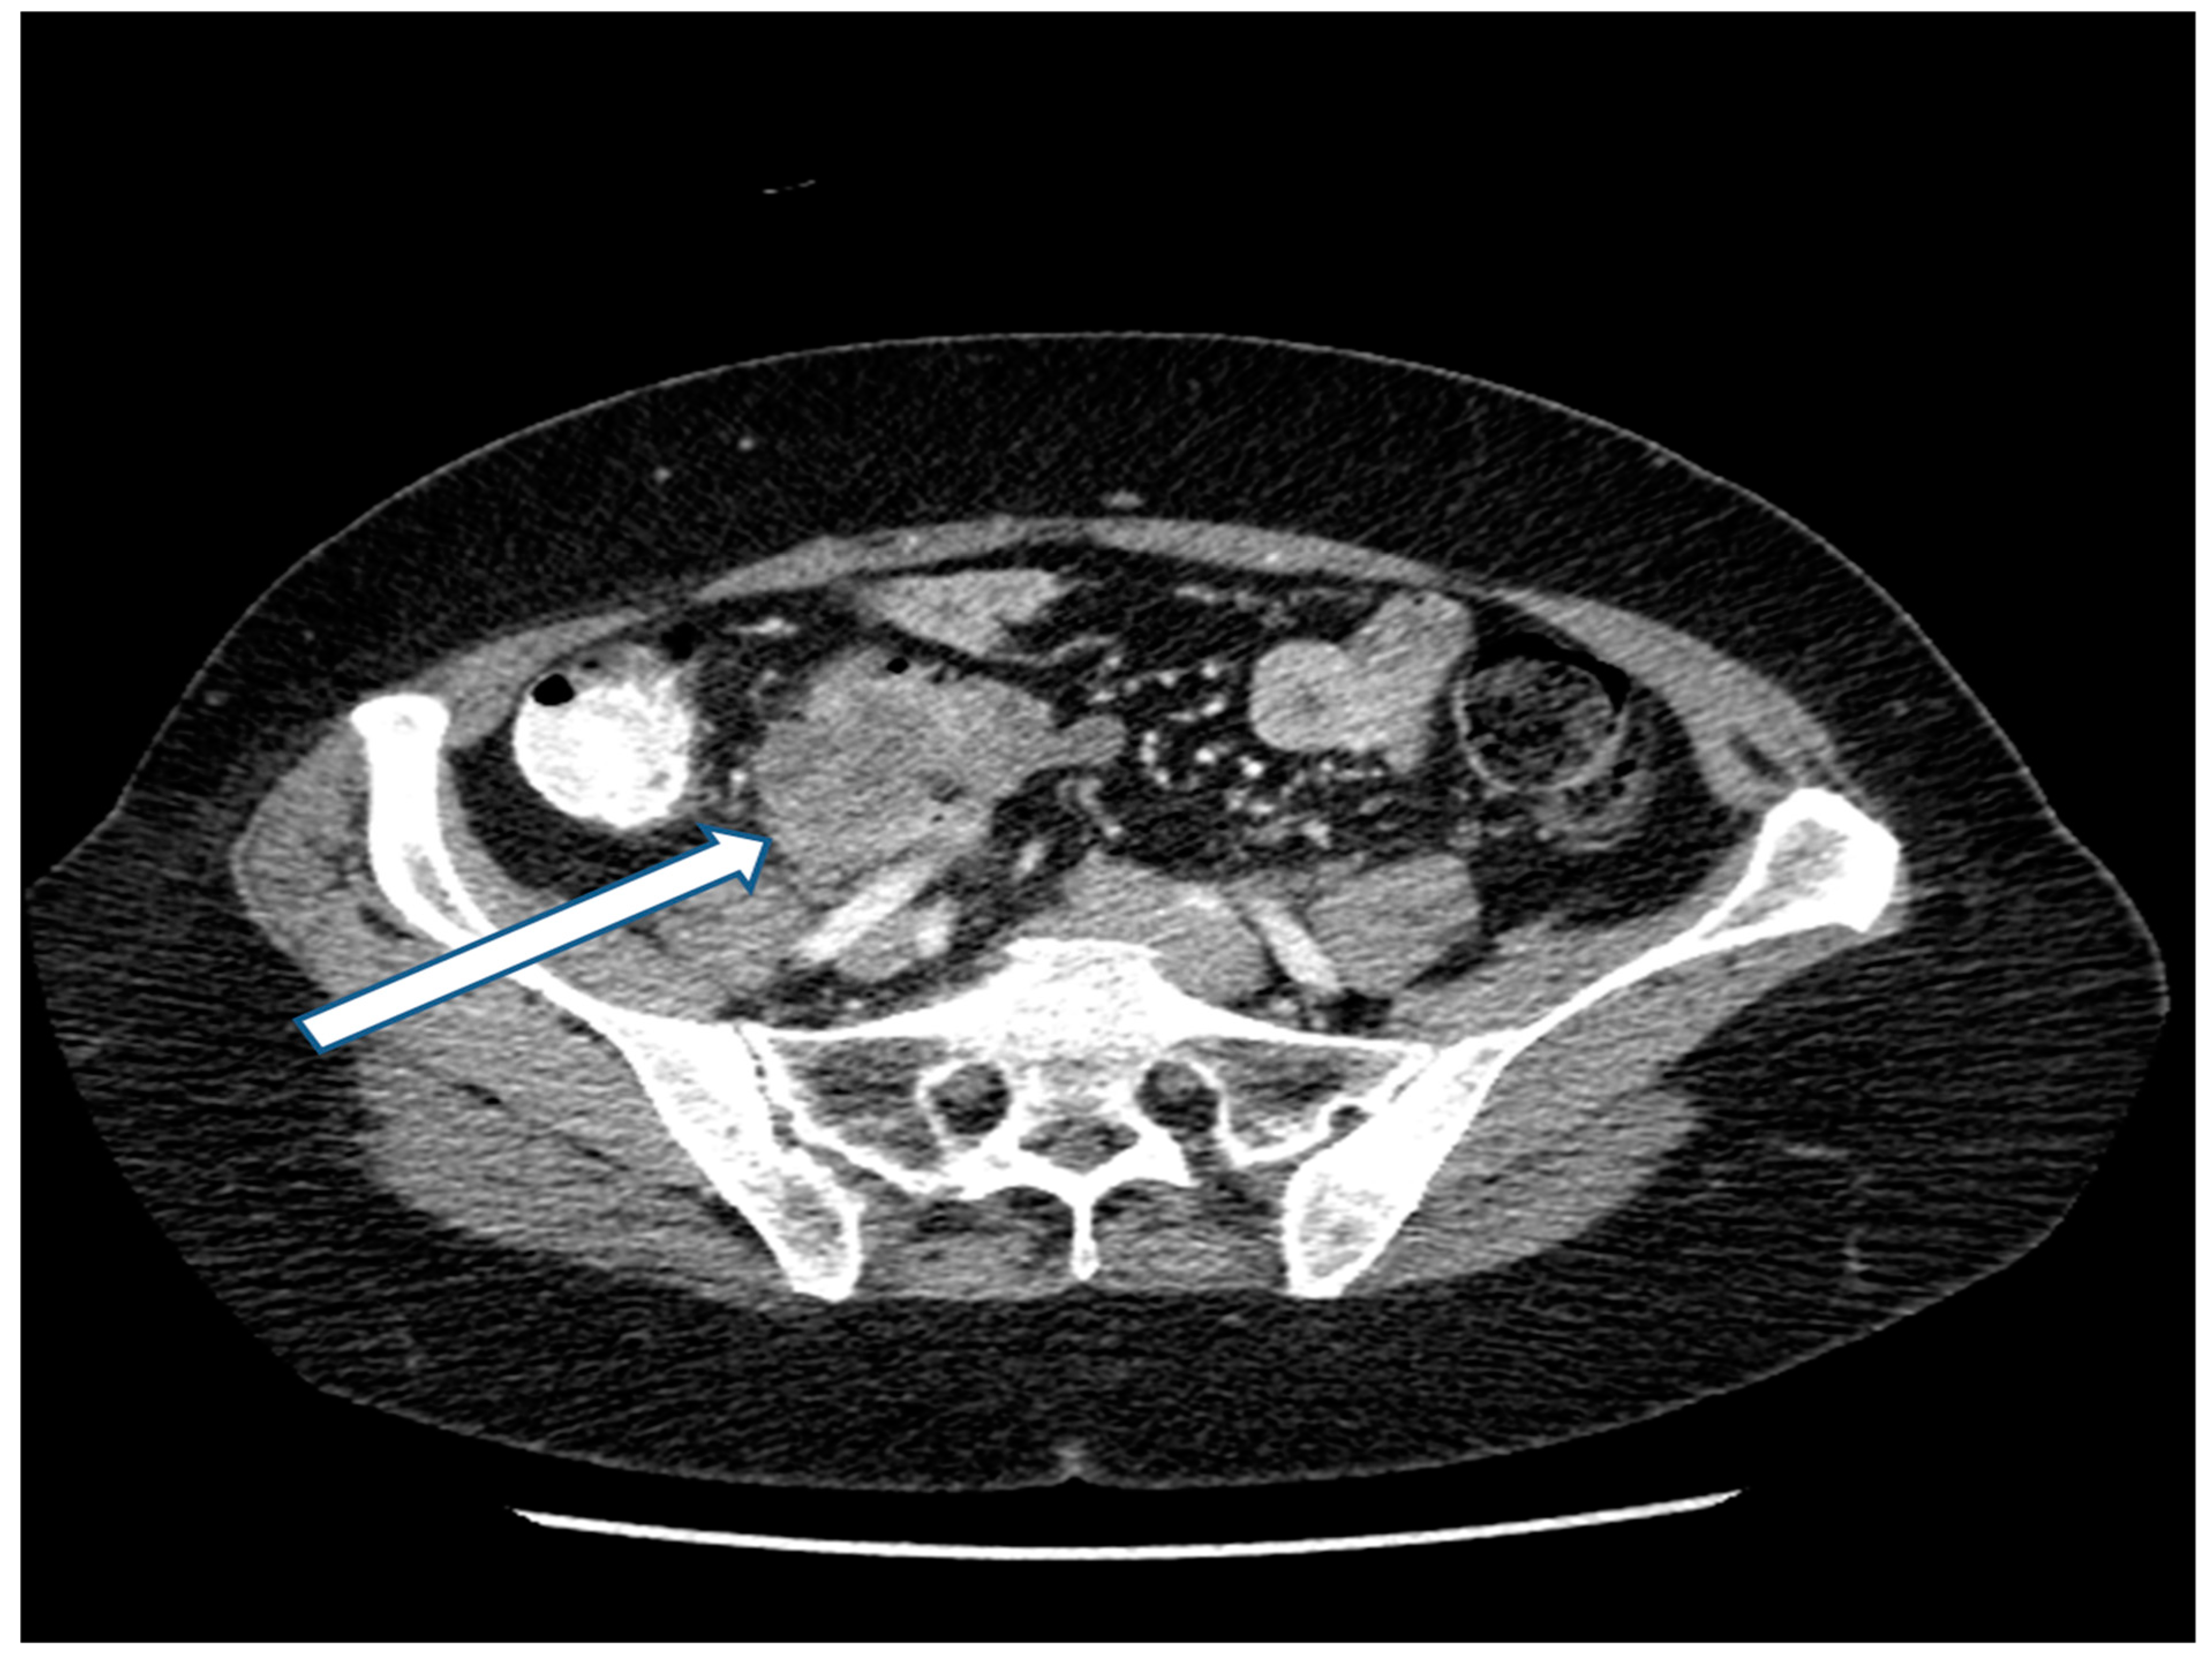

27 May 2018: Patient was asymptomatic. CEA increased from 3.0 to 20 ng/mL. CT showed a mass in the left paracolic gutter. Biopsy of this mass showed adenocarcinoma. A 1.5 cm mass was present at the ileocolic anastomotic site (Figure 2). A second mass was demonstrated in the rectovesical space (Figure 3). FOLFIRI was initiated. CEA increased to 74 ng/mL.

Figure 3. CT demonstration at the time of recurrence of a mass in the rectovesical space.